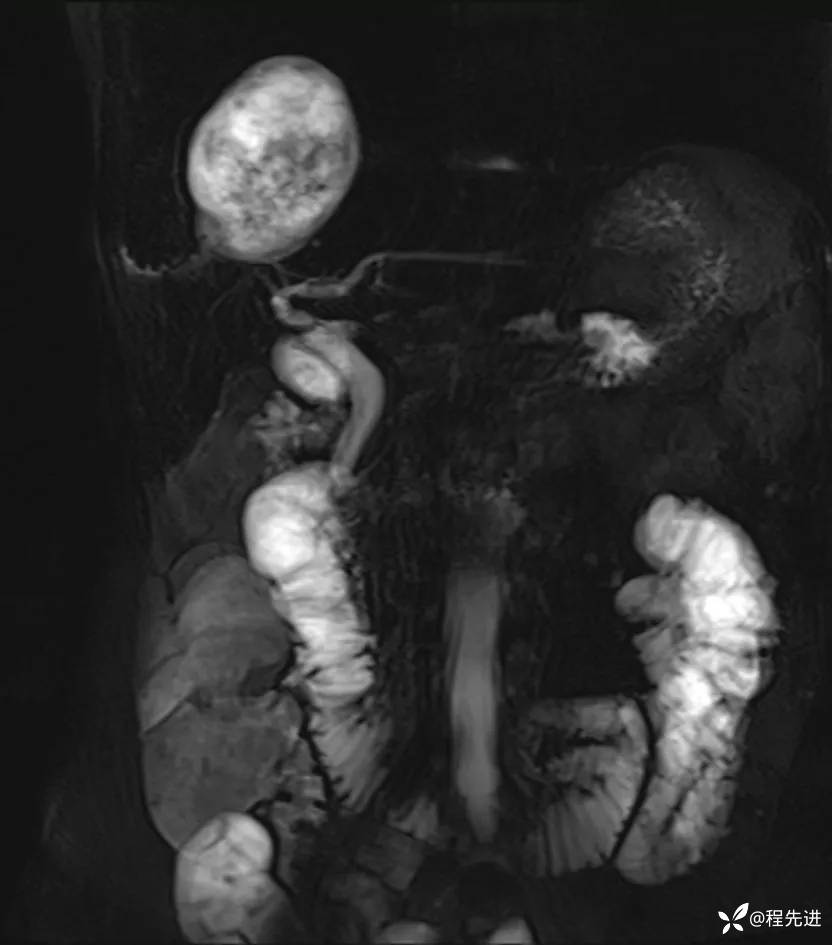

MRI平扫+增强: